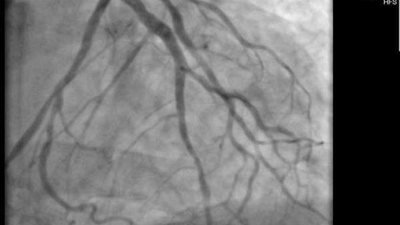

إجراء 3247 عملية قلب مفتوح وقسطرة علاجية ضمن "طمن قلبك" بالمنوفية